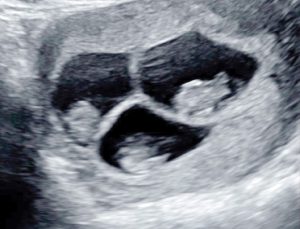

La ecografía reveladora

“Fuimos a la ecografía a conocer a nuestra guagua. Cuando el doctor comienza a mover el ecógrafo, nos dice “¡uhhh, son dos!”. En ese momento Jonathan me aprieta la mano y yo no sé explicar lo que sentí. El doctor da vuelta el monitor para poder terminar de examinar a la segunda guagua, y nos dice: “¡no son dos, son tres!”. Me acuerdo que pasaron 10 segundos, que para mí fue como un año de silencio. El doctor, la enfermera, el Jonathan y yo, mirábamos en shock la pantalla con los tres puntitos que se veían juntos en una sola foto.

Yo solo pensé ¡tengo tres vidas dentro mío!”, nos cuenta Nicole.